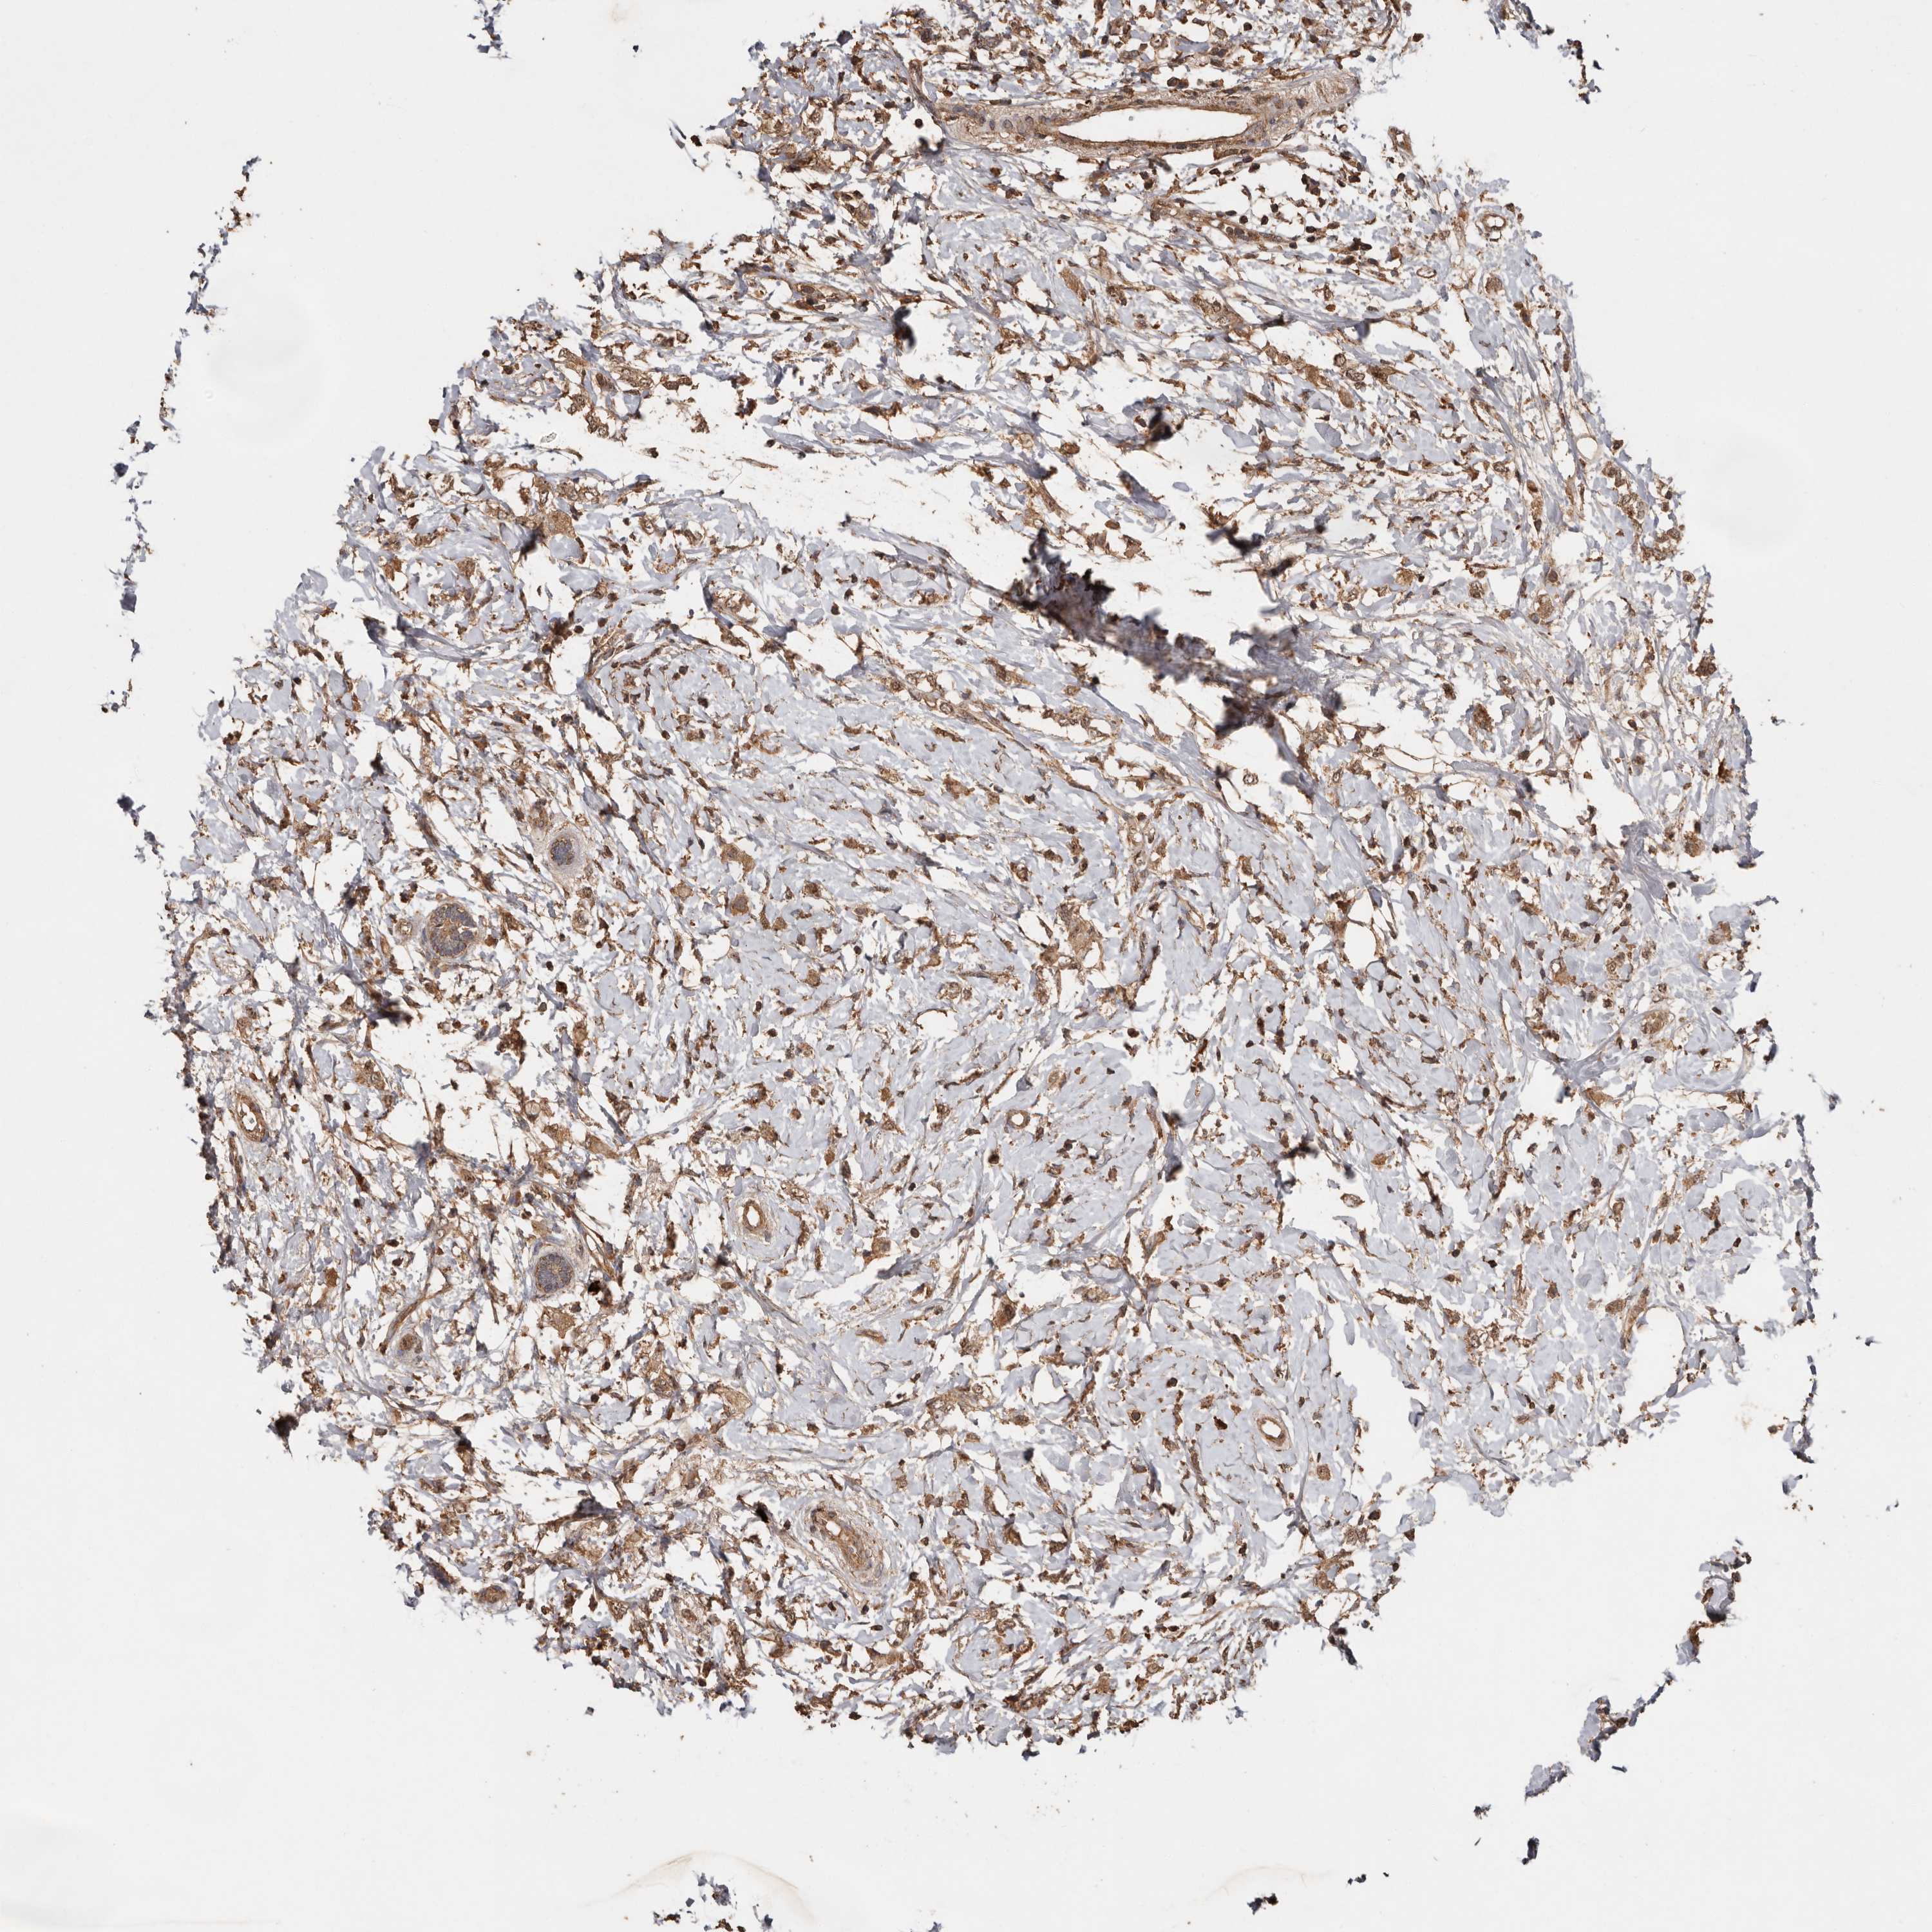

CANCER BREAST CANCER Show tissue menu

BRCA TCGA BRCA VALIDATION PROTEIN EXPRESSION